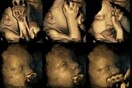

24.3.2015 Living Τι συμβαίνει στο έμβρυο όταν η μαμά καπνίζει 24.3.2015 Ερευνητές κατέγραψαν τις αντιδράσεις